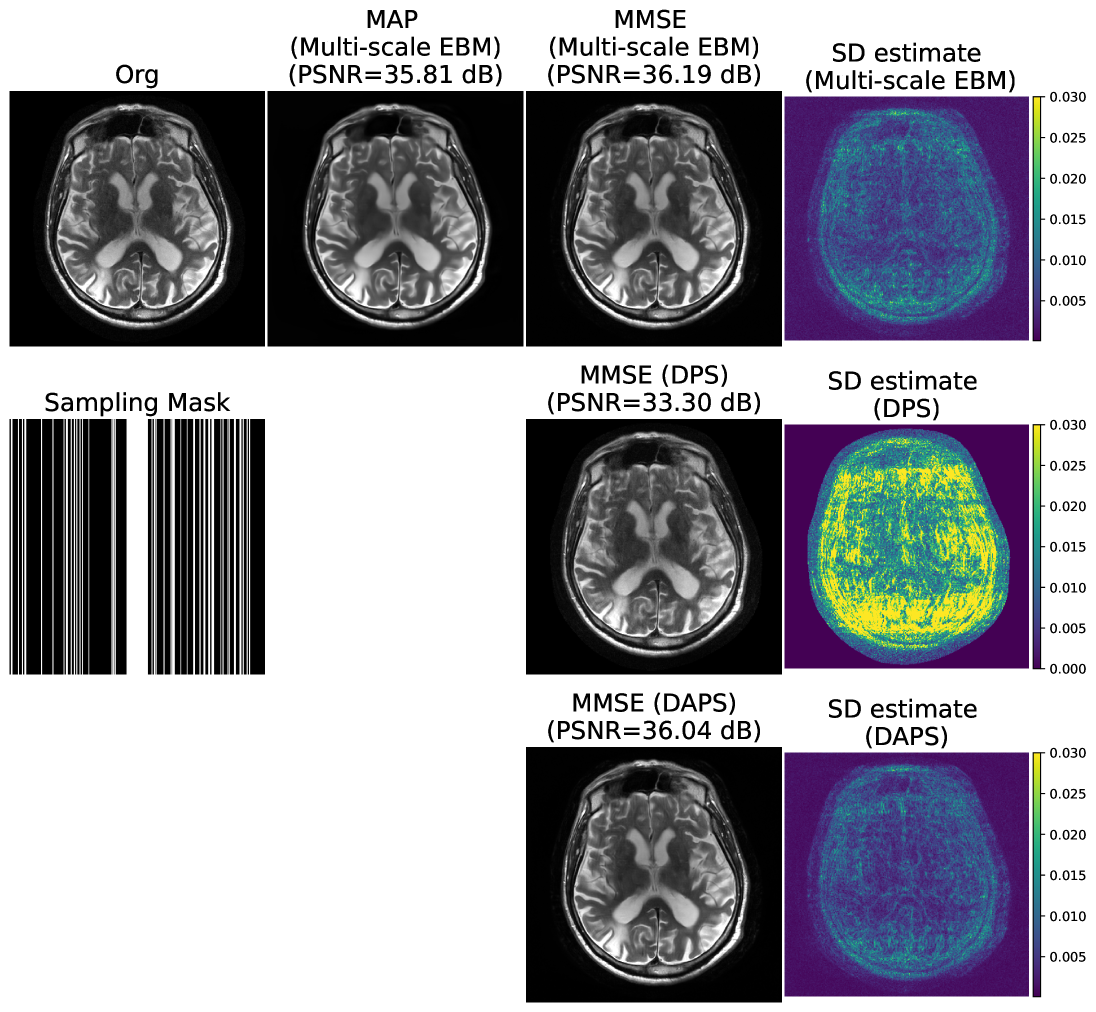

4.2.2 MRI image reconstruction

We evaluate multi-scale EBMs for MRI reconstruction from undersampled measurements at two acceleration factors. EBMs were distilled from the diffusion model in [1] using a T2-weighted brain dataset of 40,442 slices and tested on 40 slices. We compare against two diffusion-based algorithms: (a) DPS and (b) DAPS. We use the same noise scheduler as in the previous example (, , ), Langevin steps, and iterations. MMSE and uncertainty are estimated from five samples; MAP is computed via Algorithm 1 over iterations. Table 3 shows EBMs achieve performance comparable to DAPS for both accelerations. Fig. 4(a,b) illustrates reconstructions at 4× and 8×. Unlike diffusion models, EBMs provide MAP estimates without multiple samples, reducing inference cost and enabling practical clinical deployment.

While the table focuses on reconstruction quality, it is important to note that ALPS achieves these results with fewer function evaluations compared to DAPS. This efficiency stems from ALPS’s smoother trajectory from initialization to posterior, reducing the need for excessive annealing steps and iterations. Fig. 9 shows the MAP estimate and posterior sample generated via ALPS algorithm for different inverse problem. We also show the MRI reconstructions at different accelerations in Fig. 10. Fig. 11 shows the three different estimates that are given by the EBM: MAP, MMSE, and the uncertainty estimates for three different accelerations. One can observe that as the acceleration increases, the uncertainty of the reconstruction also increases. We also report the average NLPr and negative log-posterior (NLPo) values of the generated samples across different accelerations in Table 5. One can observe that as the acceleration increases, the mean NLPr and mean NLPo values decrease. This occurs because higher acceleration leads to more severe undersampling, making the reconstruction problem increasingly ill-posed. In such settings, the ALPS algorithm relies more heavily on the energy model. As a result, the algorithm outputs reconstructions with lower prior energies, and the posterior energies follow the same trend due to the reduced influence of the negative log-likelihood term.